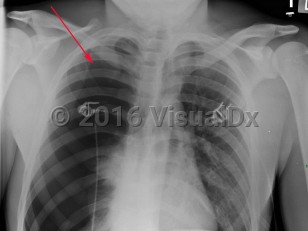

Spontaneous pneumothorax (SP) is caused by the introduction of air between the visceral and parietal pleura, typically as the result of trauma. SP can be classified as either primary or secondary. The presence or absence of lung disease distinguishes the primary form from the secondary form. Primary SP (PSP) lacks underlying lung disease, whereas secondary SP (SSP) patients have a preexisting condition such as chronic obstructive pulmonary disease (COPD; a majority of cases), cystic fibrosis, pulmonary infection, interstitial lung disease (especially histiocytosis and sarcoidosis), AIDS, neoplasms, or drug use.

The size of the pneumothorax, rate of development, and underlying clinical status determine the clinical presentation. Those with a mild PSP may not seek care, while those with SSP present acutely. The range of signs and symptoms include acute pleuritic chest pain (localized to the side of the pneumothorax), dyspnea, decreased breath sounds, tachypnea, tachycardia, hyperresonance, unilaterally decreased lung sounds, or acute decompensation.

Tension pneumothorax (TP), while rare, may result from an SP. TP, a life-threatening condition, is caused by pressurized air in the pleural space that displaces mediastinal structures and compromises cardiopulmonary function.